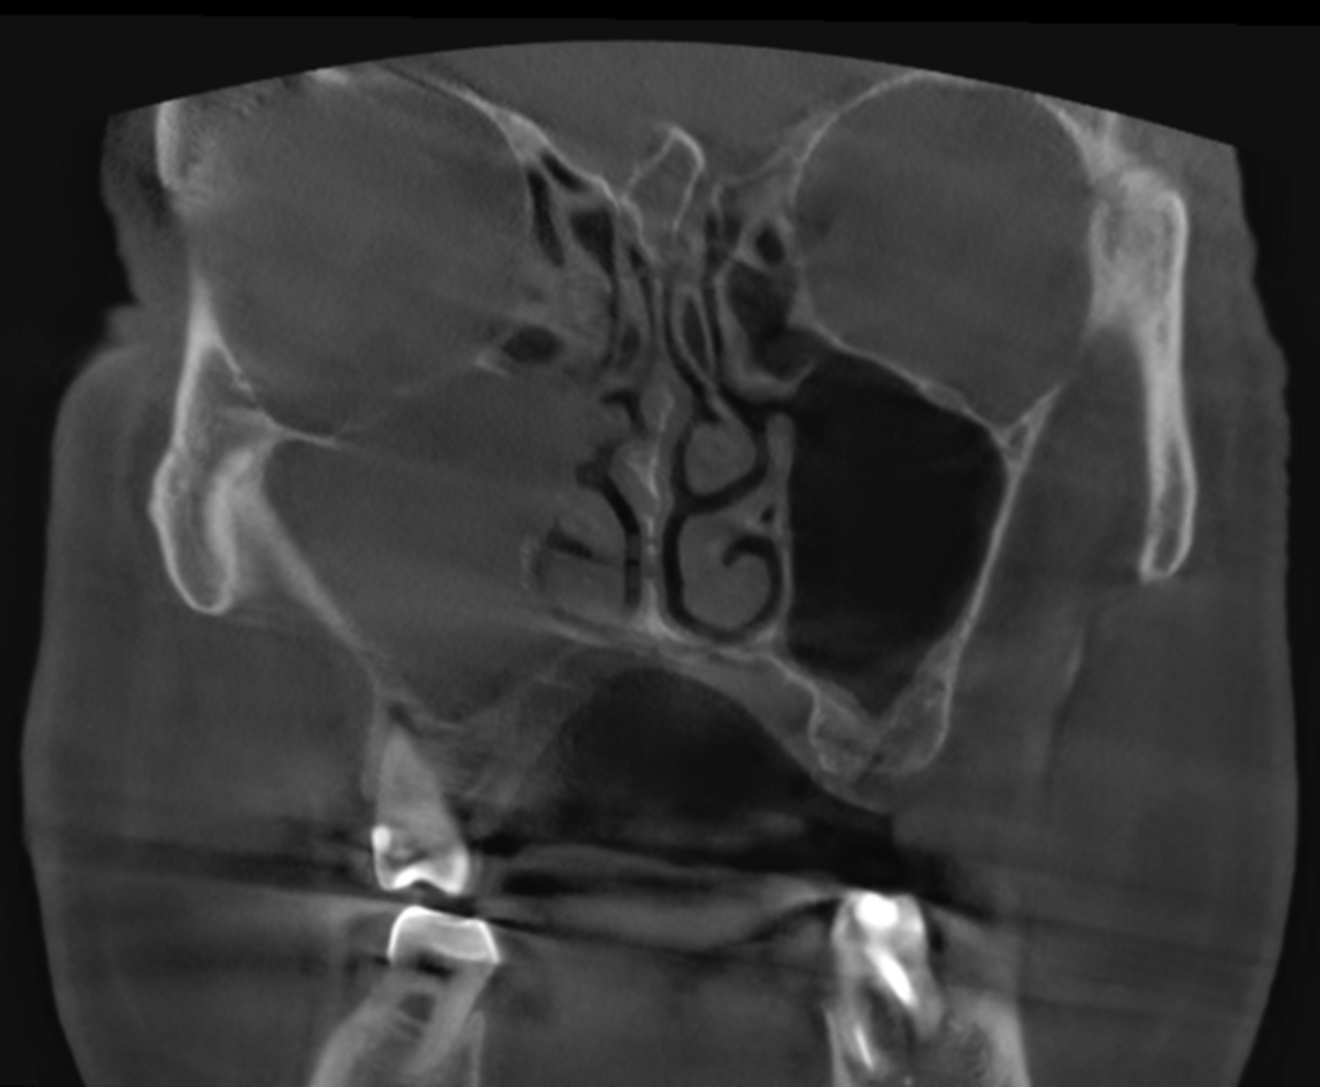

Fig. 3: Large-volume CBCT scan, frontal cross-section showing increased radiopacity in the paranasal sinus area.

The extent of the inflammation was shocking (Figs. 2a & b). Not only the maxillary sinus (Fig. 3) but the ethmoid and sphenoid sinuses too were involved, and the inflammation had spread towards the right cavernous sinus as well (Fig. 4). At this point, extraction may have been the first choice for most dental clinicians, but we had to keep in mind that invasive treatment may have increased the risk of cavernous sinus thrombosis, a potentially avoidable possibility. There are very few circumstances under which a dental procedure can cause very severe or even lethal consequences, but this case approached such a situation.

As a first step, we informed the patient about our findings on the new CBCT scan and explained the severity of his dental condition and paranasal sinusitis (Figs. 5a-f). We immediately referred him to a hospital otolaryngology department for microbial examination and proper antibiotic treatment. After nine days of a high-dose amoxicillin and clavulanic acid therapy, the endodontic treatment could be started.